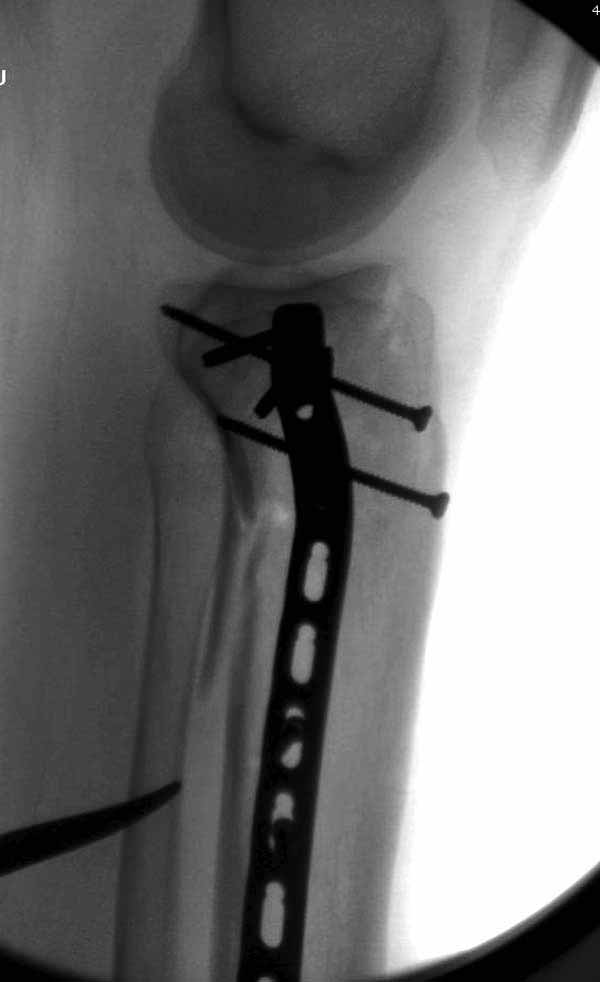

Двухколоннный перелом тибиал плато с вовлечением проксимального диафиза. Внутрисуставной компонент без смещения, и такой перелом можно лечить любым из описанных методов, о которых говорят наши коллеги.

Удобно аппаратом Илизарова или интрамедуллярным гвоздем. Гвозди не так сложно, как пугают, тем более Александр готов помощь с методичкой. Сперва надо установить компрессирующие шурупы на мыщелки. Давно отказались в пользу 3.5-4.0 мм кортикальных вместо толстых спонгиозных, потому что не доказаны преимущества толстых шурупов. Тонкие шурупы в субхондральной зоне смотрятся намного элегантнее, чем толстые 6.5.

Это мероприятие превращает перелом в простой диафизарный, который легко можно фиксировать гвоздем. Шурупы надо установить сзади предполагаемого места введения гвоздя.

В приложении этапы фиксации Both Column Fx и пластиной Synthes для плеча при переломе медиального мыщелка.